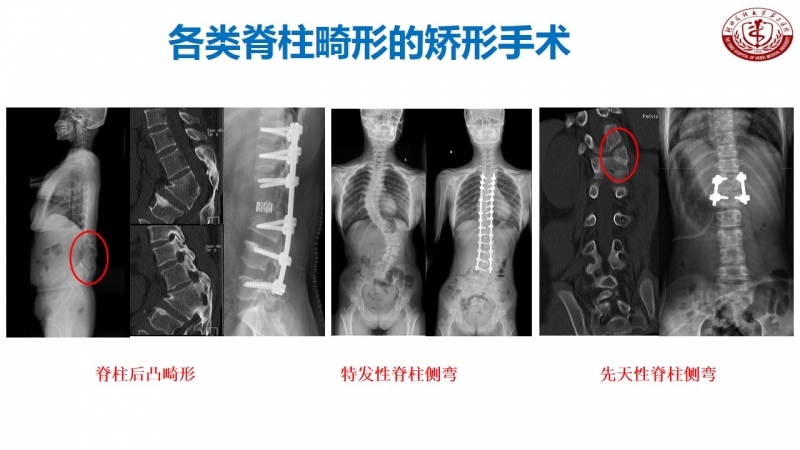

作为脊柱外科的主任,丁文元教授时刻不忘科室的建设和发展。目前,河北医科大学第三医院脊柱外科共有33人,其中主任医师9人,副主任医师4人,主治医师11人,分三个病区,共120张床位,年门诊量66000余人次,年手术量4500余台,并开展了一系列脊柱高难手术,如复杂脊柱畸形截骨矫形术、复杂严重颈椎病前后路手术、胸腰椎前后路手术、上颈椎腰骶部复杂手术以及脊柱各种微创手术。

脊柱外科目前所开展的诊疗技术(滑动查看)